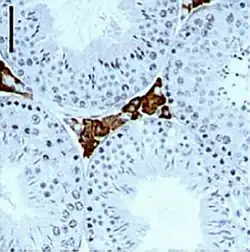

![]() Células de Leydig en marrón (flecha). Túbulos en celeste. | ||

Las células de Leydig o células intersticiales del testículo[1] son las células secretoras endócrinas encargadas de secretar cerca del 90 % de la hormona masculina (testosterona), están localizadas en el compartimento intersticial entre los túbulos seminíferos del testículo.

Las células de Leydig están ubicadas en el espacio entre los túbulos seminíferos llamado compartimento intersticial, se encuentran rodeadas por el tejido conjuntivo laxo, con microvasculatura. Por su función endócrina, corresponden al parénquima ya que secrecretan la hormona masculina testosterona.[2][3]

Con el microscopio óptico, las células intersticiales secretoras de Leydig, tienen forma redondeada o poligonal con un diámetro de 15-20 micrómetros (μm).

Con la tinción clásica de H&E, el citoplasma se visualiza rosado (eosinofílico). También es rico en inclusiones lipídicas que se ven blancas.

En su interior se alojan los cristales de Reinke cuerpos de contenido proteico.

Se ven agrupamientos de estas células secretoras dentro del intersticio intertubular, en estrecha cercanía de los capilares sanguíneos.[3]